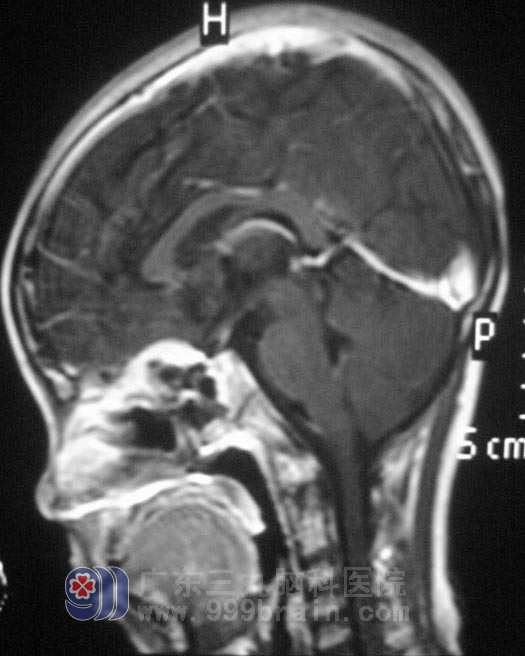

MR检查提示鞍区巨大占位性病变,大小约25.6mm×29.2mm×28.5mm,压迫视神经及周围组织。眼科专家会诊,小宛双眼均无光感,瞳孔直径约5.0mm,双眼对光反射消失。鲁明主任考虑到小宛起病急,视力巨降,经过缜密的准备后,9月22日在全麻下行经鼻蝶鞍区肿瘤切除术,术中暴露蝶窦后见灰白色肿瘤,质韧,不易剔除,血供丰富,蝶窦内、鞍底骨质破坏,在显微镜下予肿瘤切除。术后小宛的瞳孔恢复正常,没有头痛不适,已经转入放疗科行进一步治疗。术后病理结果为:(鞍区)腺泡状横纹肌肉瘤并大面积坏死。http://www.999brain.com/

▲手术后